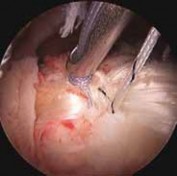

FIG 5 • Arthroscopic débridement of a partial-thickness tear.

2. Arthroscopic débridement is an initial component of nearly every biceps tendon surgical procedure.

1. In cases of fraying or partial tearing, débridement alone may be adequate to eliminate its contribution as a pain generator (

FIG 5

).

2. This is particularly true in cases in which the preoperative workup did not suggest the biceps as a significant component of patient symptoms, and when concomitant pathology may otherwise explain the patient’s presentation.